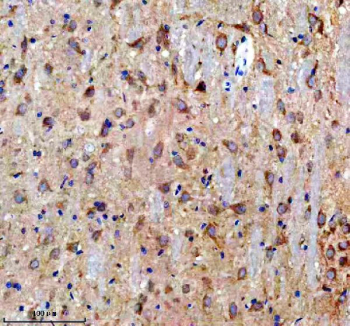

Immunohistochemistry analysis of Doublecortin-like kinase 1 using Doublecortin-like kinase 1 antibody. Doublecortin-like kinase 1 expression was examined in a paraffin-embedded section of rat brain tissue. Heat-mediated antigen retrieval was performed using EDTA buffer (pH 8.0). Tissue sections were blocked with normal goat serum and incubated with Doublecortin-like kinase 1 antibody overnight at 4°C. Immunoreactivity was detected using an HRP-based detection system with DAB chromogen, followed by hematoxylin counterstaining.

Immunohistochemistry analysis of Doublecortin-like kinase 1 using Doublecortin-like kinase 1 antibody. Doublecortin-like kinase 1 expression was examined in a paraffin-embedded section of human glioma tissue. Heat-mediated antigen retrieval was performed using EDTA buffer (pH 8.0). Tissue sections were blocked with normal goat serum prior to incubation with Doublecortin-like kinase 1 antibody overnight at 4°C. Signal was visualized using an HRP-based detection system with DAB chromogen, followed by hematoxylin counterstaining.